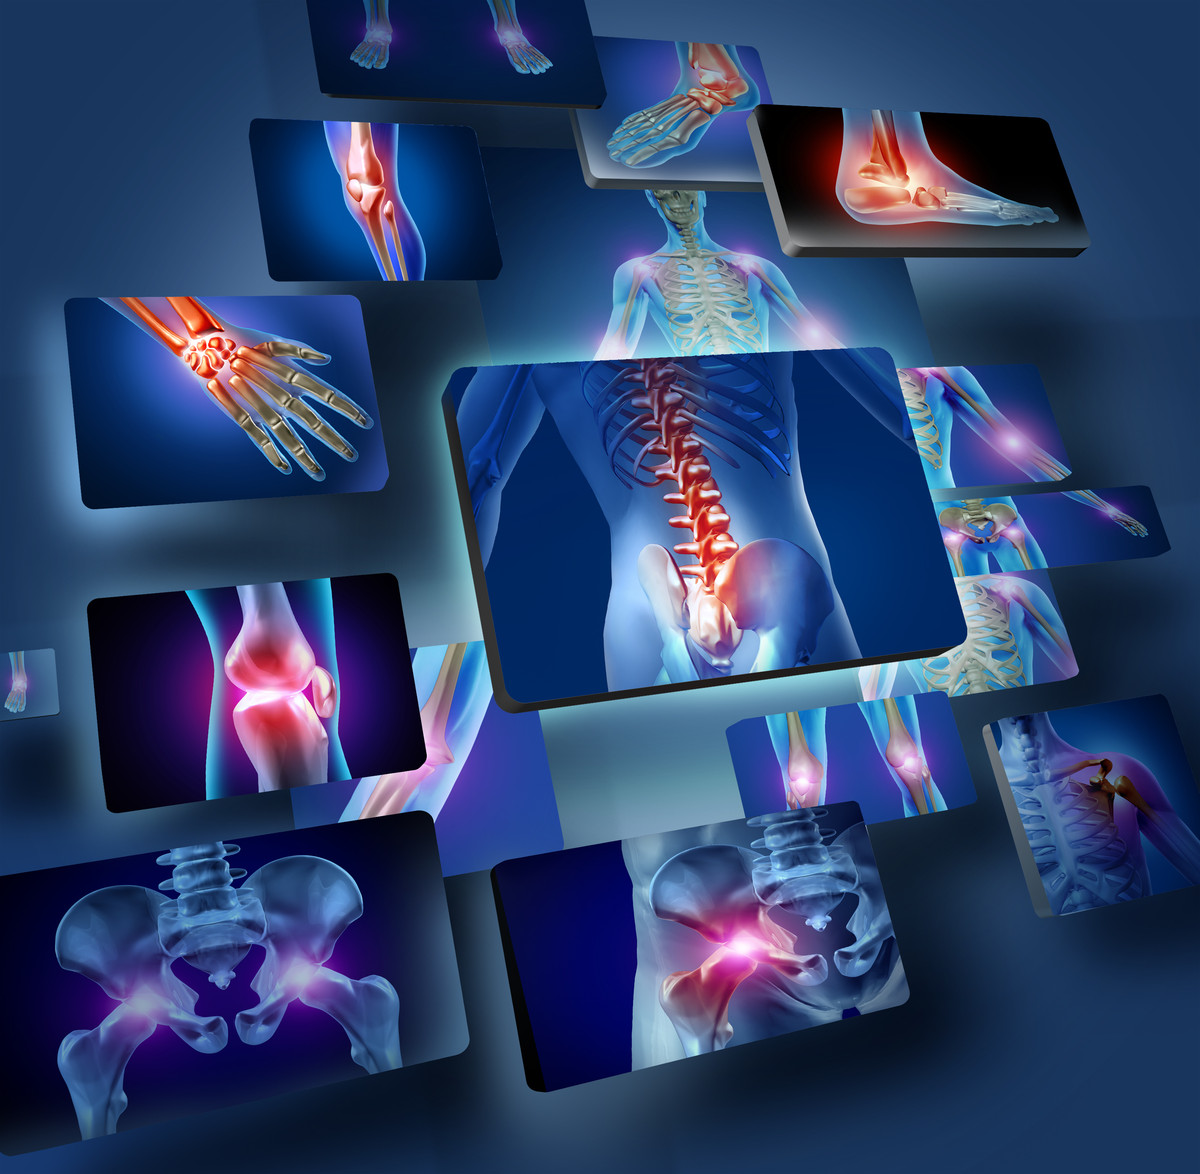

Анатомические рисунки суставов человека